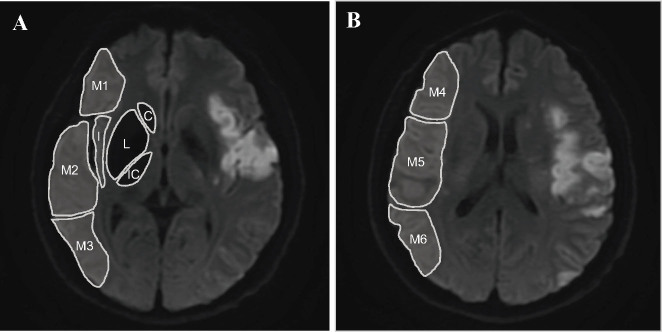

Materials and methods: Consecutive patients with AIS and anterior circulation large-vessel stenosis and occlusion between January 2019 and December 2020 were included. The ASPECTS score and subregion involvement for each patient was assessed using posttreatment magnetic resonance diffusion-weighted imaging. Univariate and multivariable regression analyses were conducted to identify subregions related to 3-month poor functional outcome (modified Rankin Scale scores, 3-6) in the reperfusion and medical therapy cohorts, respectively. In addition, prognostic efficiency between the region-based ASPECTS and ASPECTS score methods were compared using receiver operating characteristic curves and DeLong's test.

Results: A total of 365 patients (median age, 64 years; 70% men) were included, of whom 169 had poor outcomes. In the reperfusion therapy cohort, multivariable regression analyses revealed that the involvement of the left M4 cortical region in left-hemisphere stroke (adjusted odds ratio [aOR] 5.39, 95% confidence interval [CI] 1.53-19.02) and the involvement of the right M3 cortical region in right-hemisphere stroke (aOR 4.21, 95% CI 1.05-16.78) were independently associated with poor functional outcomes. In the medical therapy cohort, left-hemisphere stroke with left M5 cortical region (aOR 2.87, 95% CI 1.08-7.59) and caudate nucleus (aOR 3.14, 95% CI 1.00-9.85) involved and right-hemisphere stroke with right M3 cortical region (aOR 4.15, 95% CI 1.29-8.18) and internal capsule (aOR 3.94, 95% CI 1.22-12.78) affected were related to the increased risks of poststroke disability. In addition, region-based ASPECTS significantly improved the prognostic efficiency compared with the conventional ASPECTS score method.